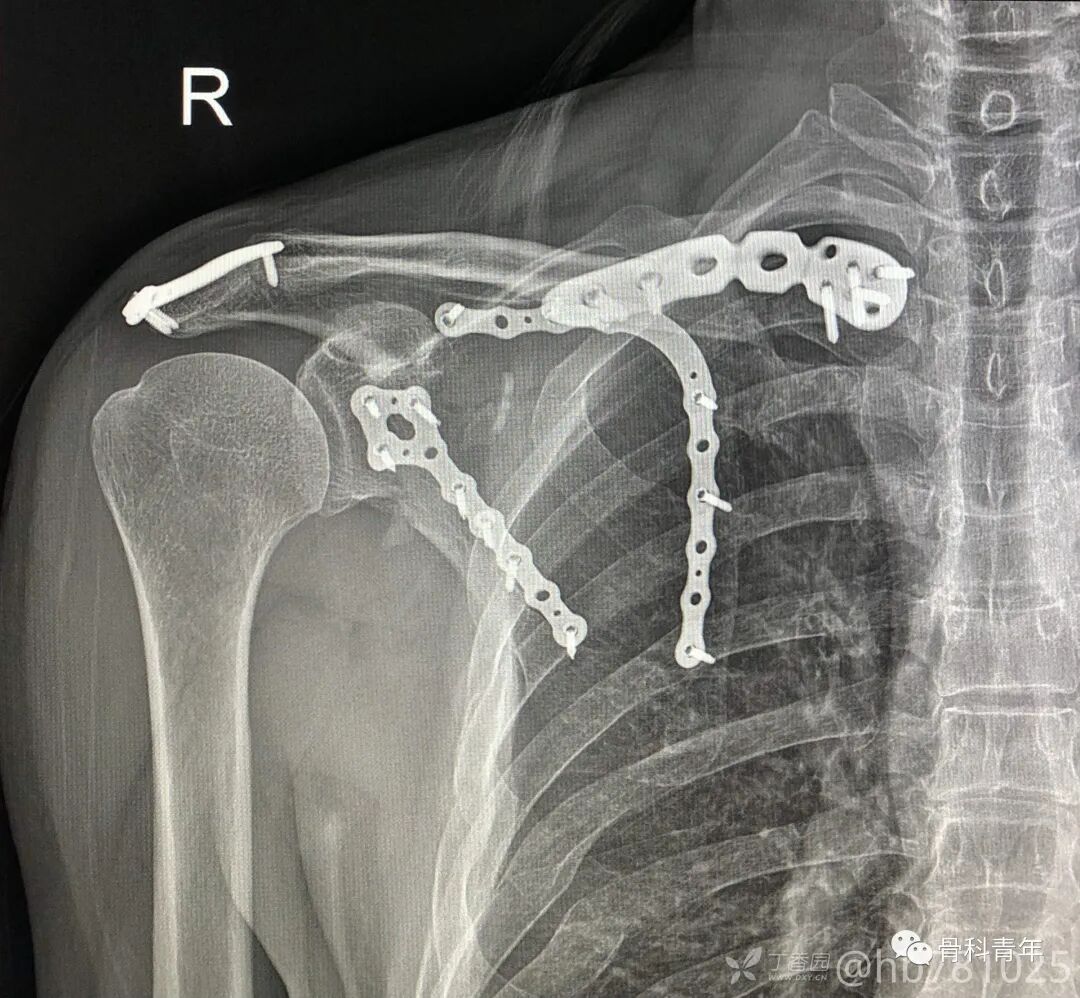

22.漂浮肩